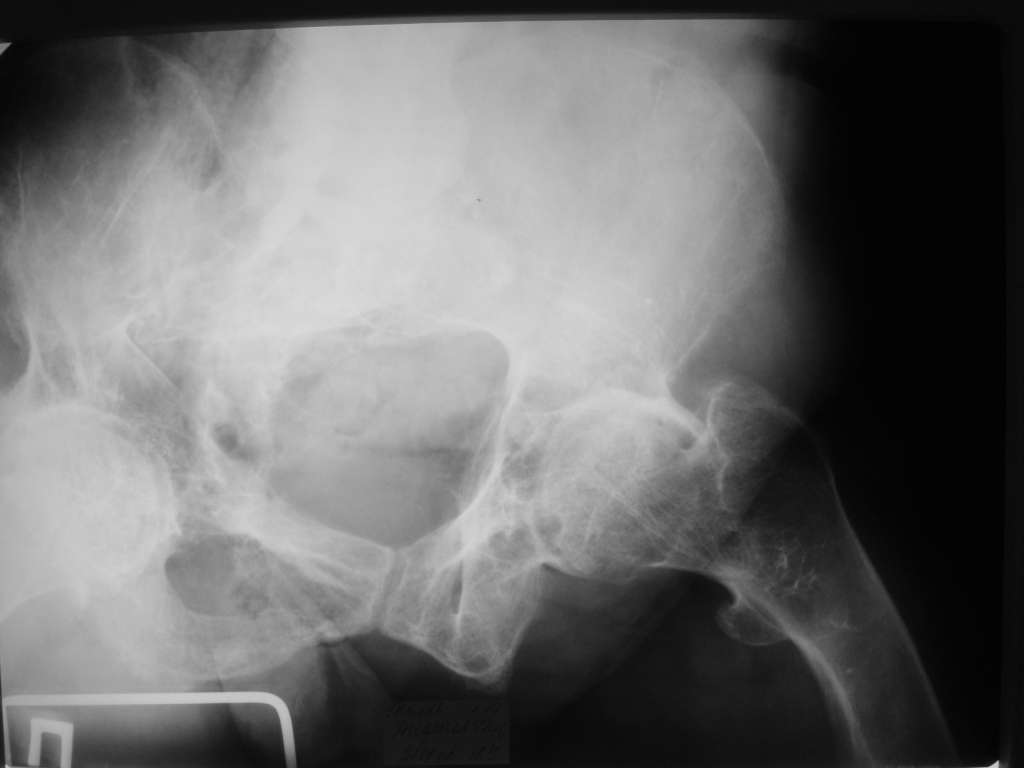

Уважаемые коллеги! Здравствуйте! Прошу у Вас совета вот по какому случаю.В нашу клинику поступила женщина 71 год. Травма в результате ДТП. (Пациентка передвигалась на инвалидной каляске и была сбита автомобилем). Диагноз: Множественная травма. Перелом нижней трети правого бедра. Перелом средней трети правой б/берцовой, малоберцовой кости, нижней трети левой большоберцовой, м/берцовой кости.Травматический шок. Со стороны внутренних органов и систем без патологии. Больная госпитализирована в реанимационное отделение, где было наложено двойное скелетное вытяжение за правую н/конечность. Левая н/конечность иммобилизована гипсовой лонгетой. Из анамнеза: больная является инвалидом 1 группы по опорно-двигательному аппарату. В детстве перенесла рахит. Осложнением которого "О" образная деформация нижних конечностей. Ограничено отведение нижних конечностей, деформирующий артроз тазобедренных и коленных суставов. В 1990 году перелом правого бедра остеосинтез пластиной. После операции больная передвигалась только на костылях или в инвалидной коляске.

Контрольные рентгенограммы прилагаю.

Судя по Ro-граммах у больной скорее всего Vit-D

резистентный рахит и его последствия.Имеем наблюдения лечения остеопороза у данного контингента больных активными формами Vit-D -кальцитриол,даже в таком возрасте (положытельные результаты уже через 1-2 мес.).Фиксация фрагментов возможна внеочеговым аппаратом (самонарезные стержни в аппарате Илизарова).